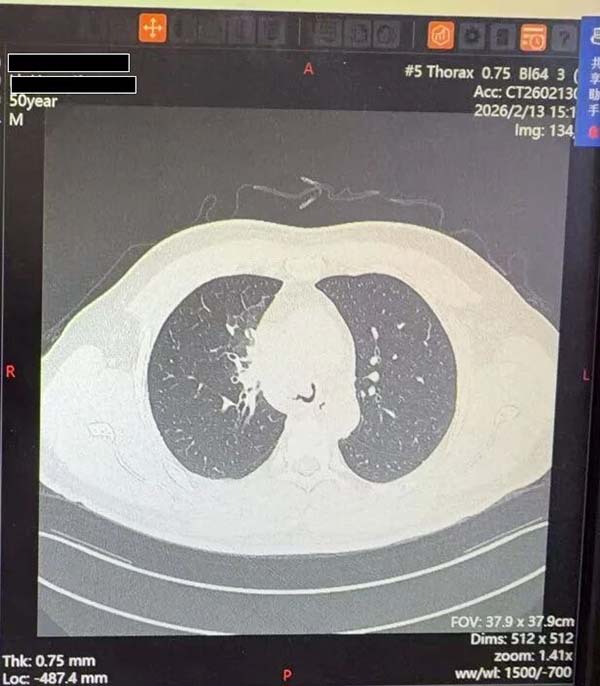

一名50岁男性患者于2024年7月确诊晚期肺癌,经过1.5年靶向治疗后,近一个月突然出现严重呼吸困难,甚至无法平卧,被紧急收治于北京朝阳医院呼吸三病区。肺CT检查结果显示:气管下段隆突上占位性病变,右主支气管完全堵塞,左主支气管狭窄程度超过90%,仅余一丝缝隙维持通气。“这是恶性中央气道梗阻中最凶险的类型,患者随时可能因窒息死亡。”呼吸肿瘤专业组团队主任医师张予辉、副主任医师朱敏介绍,肿瘤巨大占位不仅堵塞呼吸通道,还因血供丰富增加了术中出血风险。结合患者病情急、梗阻重、基础病复杂的特点,医院立即启动多学科会诊(MDT)机制,呼吸与危重症医学中心、麻醉手术中心等核心科室专家迅速集结,在春节假期的特殊时段制定了“硬质气管镜下氩气刀、激光肿瘤消融清除术”的紧急救治方案。

肺CT检查显示:气管下段隆突上占位性病变,右主支气管完全堵塞,左主支气管狭窄程度超过90%